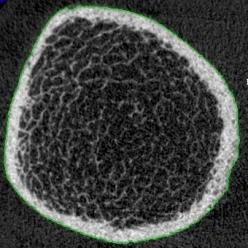

Osteoporosis is a disease that affects bones characterized by low bone mass and micro-architectural deterioration. Osteoporosis is an important public health concern, and early diagnosis and treatment indication is a key to effective intervention.

The goal of this project is to develop accurate diagnostic techniques based on the bone micro-architecture. We are studying the effect of osteoporosis on thethe bone architecture, and aim at providing additional information beyond the current state of the art: the measurement of bone mineral density.